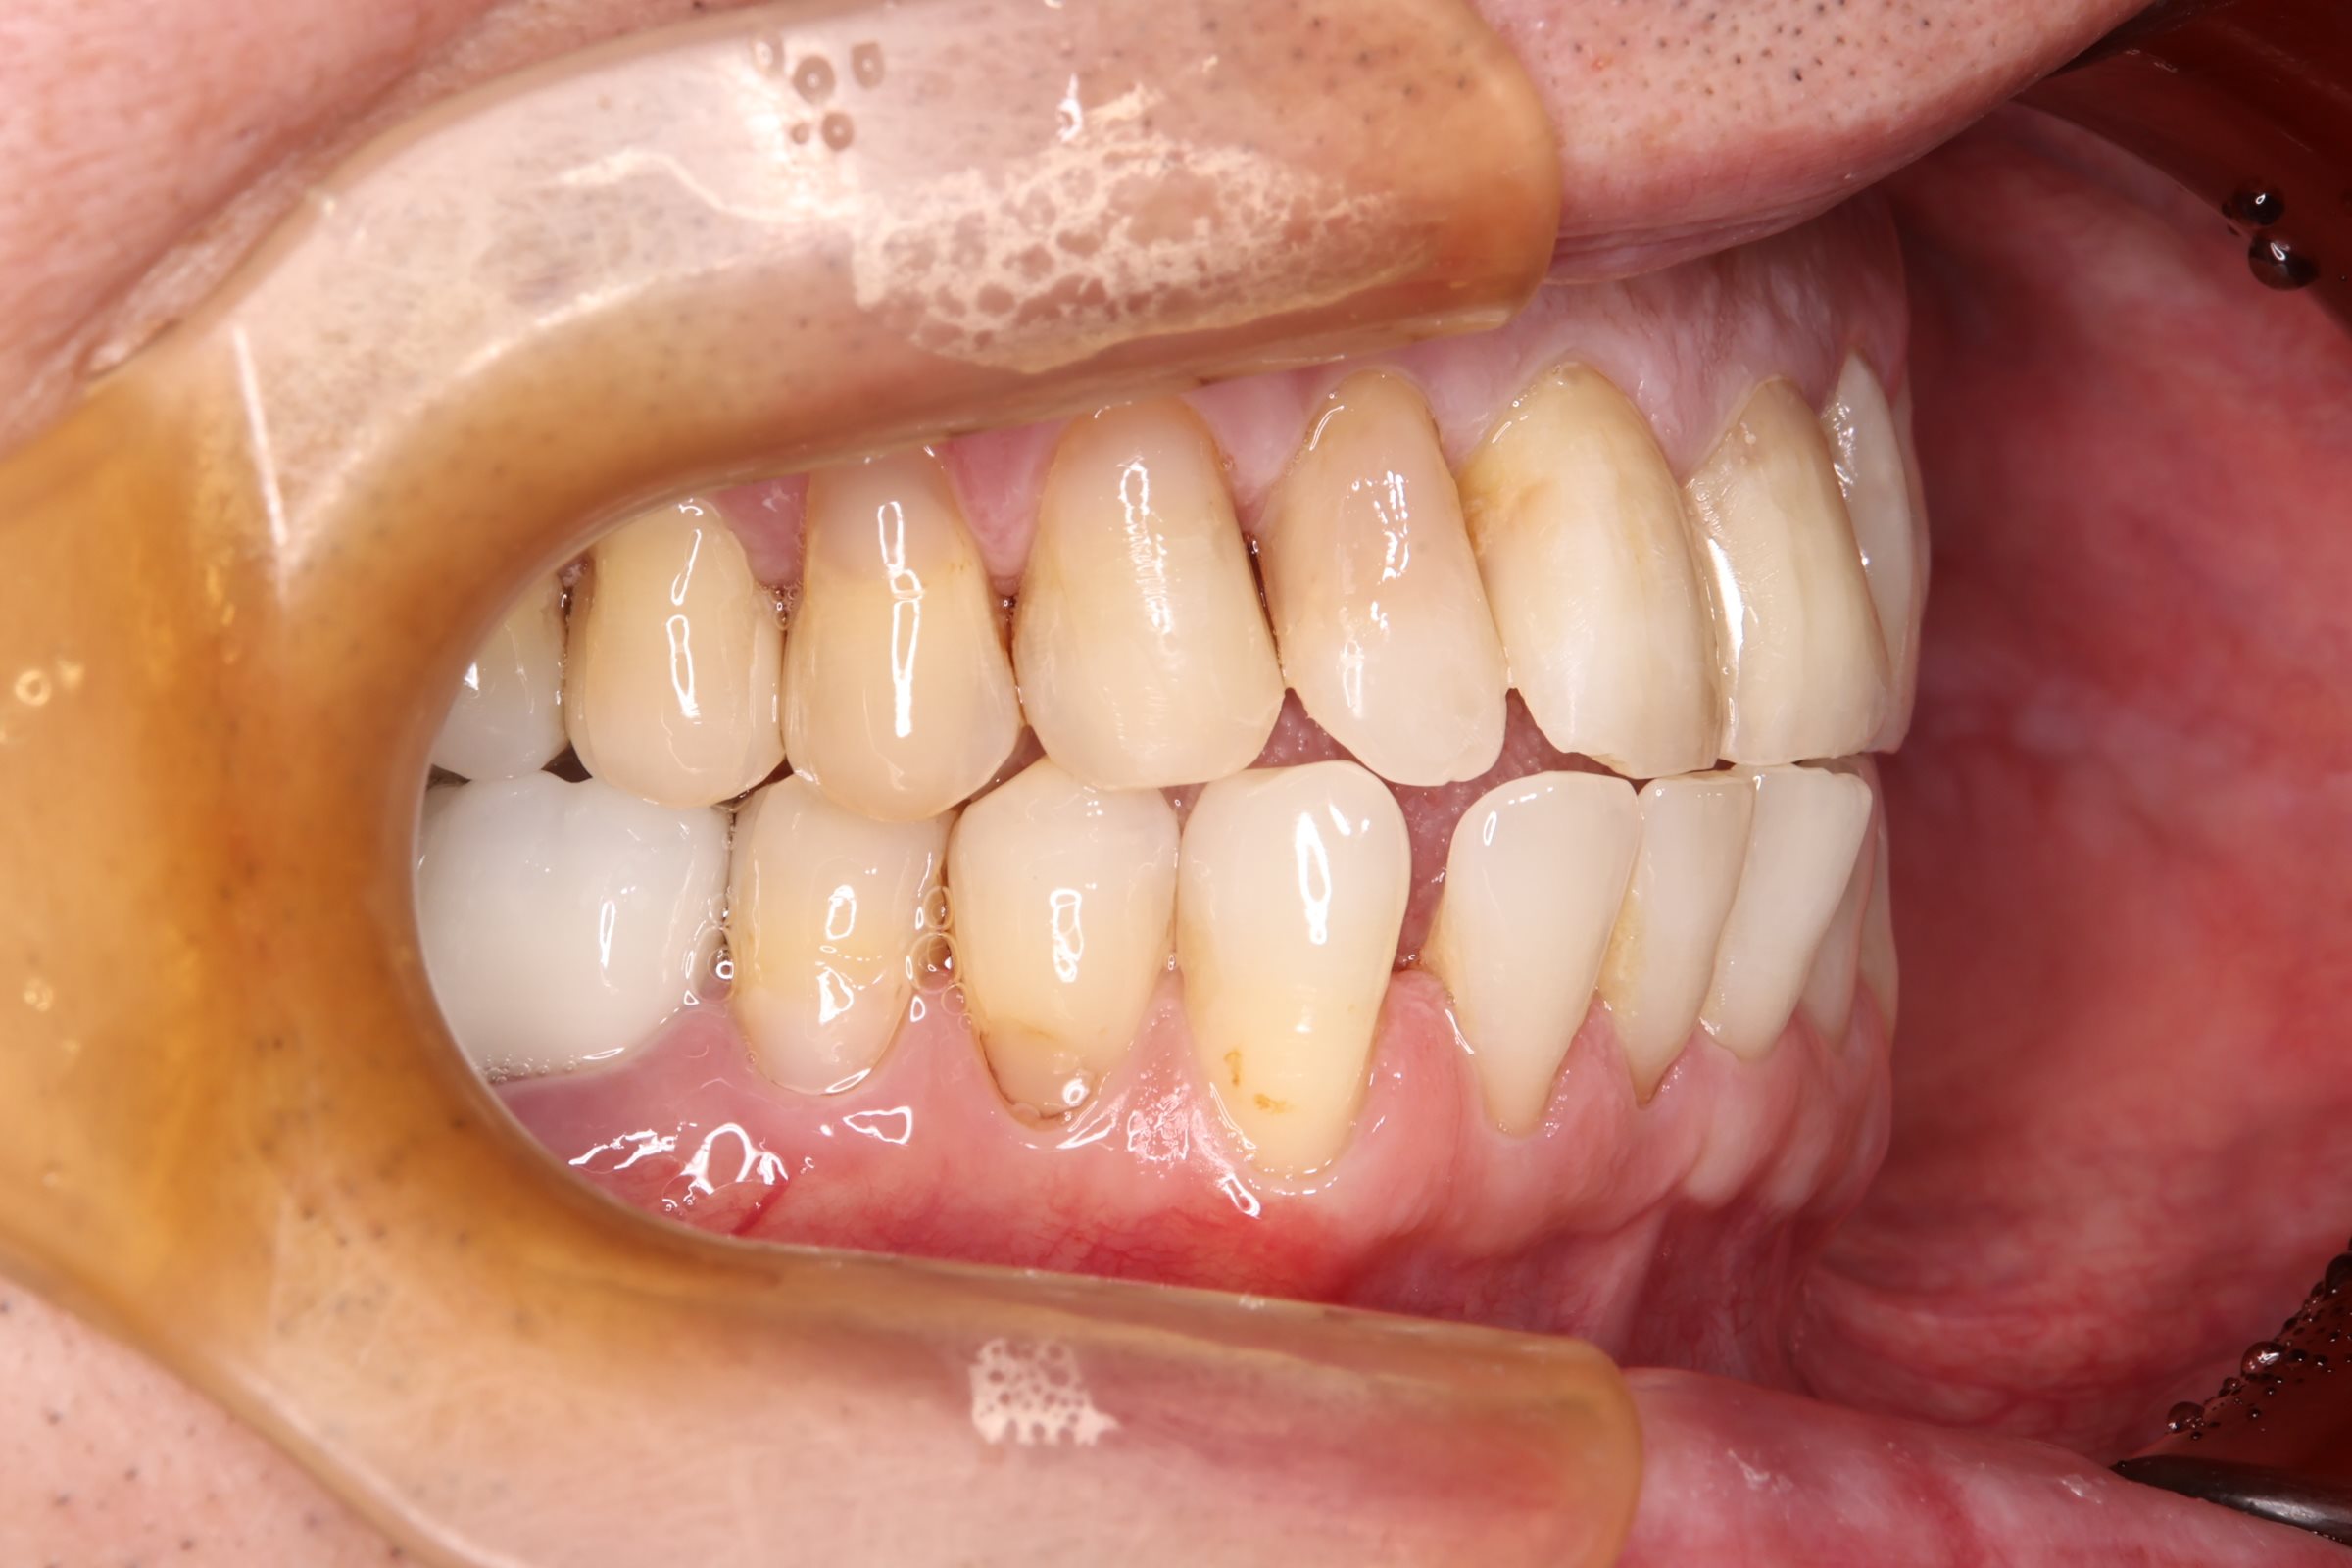

初診時の口腔内の状態:

お口全体に虫歯や歯周病の原因となるプラーク(歯垢)が多く付着していました。右上奥歯は重度の虫歯で歯冠部(歯の頭)が失われており、左下奥歯は過去の治療箇所から細菌が入り込み、根の先に炎症が起きている状態でした。

また、左右の奥歯にはWSD(楔状欠損)があり、知覚過敏も見られました。

Before